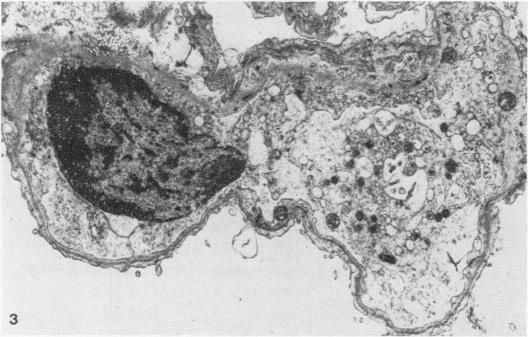

Most DBA mastocytoma and Sarcoma 180 cells trapped in the lungs of mice after i.v. injection died within 7 h. Rates of cell death were similar for both tumour cell lines. Rates of tumour cell death were unrelated to whether the cells were allogeneic or syngeneic, induced platelet aggregation or not, had different patterns of subsequent tumour growth, or were injected in varying numbers. Cell death was by coagulative necrosis, not apoptosis. Sarcoma 180 tumour cells were quickly localized in the lung and enclosed in platelet aggregates which remained, with degranulation, until the time of tumour cell death. However, platelet aggregation did not appear to play a role in tumour cell killing. The prevention of platelet aggregation by pretreatment of mice with an anticoagulant had little effect on the rate of death of tumour cells in the lung. Mastocytoma tumour cells did not cause platelet aggregation, yet died in the lung at similar rates to Sarcoma 180 cells. The killing of tumour cells in the lung did not appear to be cell-mediated. No mononuclear cells were seen in the vicinity of tumour cells and the type of cell death was not that associated with cell-mediated killing. The tumour cells did not die within 6 h of being injected into the peritoneal cavity. It is suggested that a nonspecific non-immunological process results in the death of intravenously injected tumour cells in the lung. This process was not affected by differing oxygen levels in the inhaled gas.